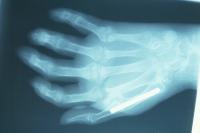

Preop films.

Click for larger image